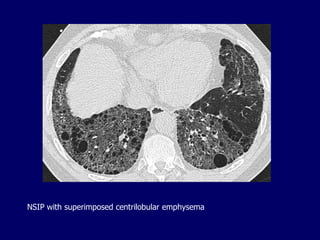

NSIP with superimposed centrilobular emphysema

NSIP with superimposedcentrilobular emphysema